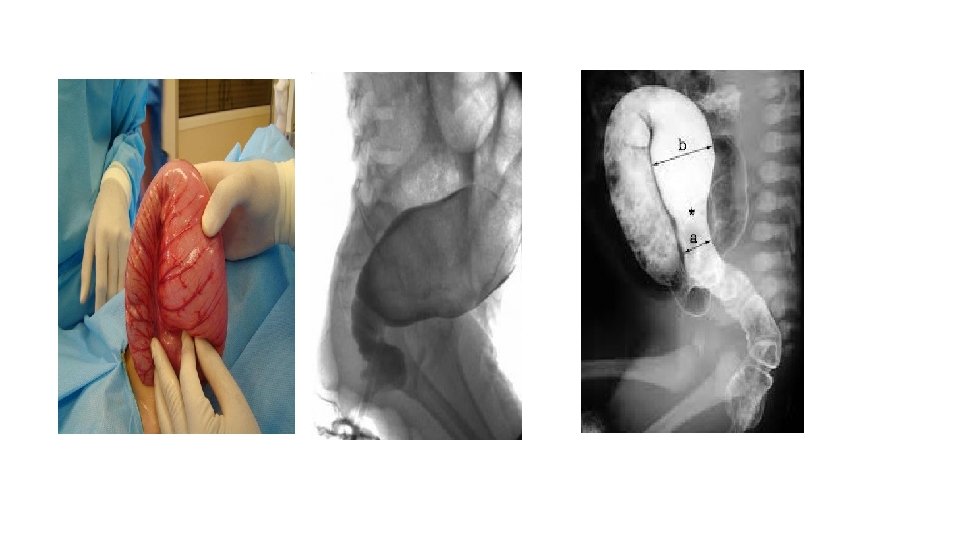

Investigation : 1) Barium enema : (Narrow segment distally, transitional zone, dilated segment proximally). Recto-sigmoid ratio less than 1 (transvers diameter of rectum / transverse diameter of sigmoid) (a/b = < 1). Retention of contrast material in the colon more than 24 hr post filming. Neonate with HD may have false negative result of contrast enema.